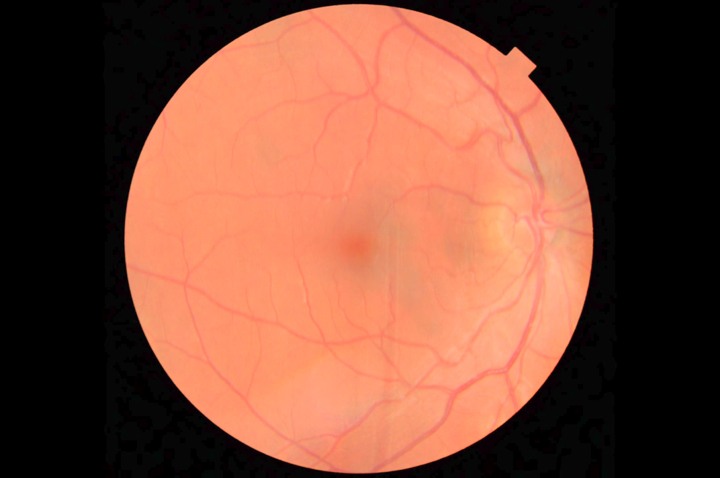

A 3D section of the layers ofthe retina and vitreous jellyA 3D section of the layers of the retina and vitreous jellyAge-related Macular Degeneration Dry FormAge-related Macular Degeneration Dry FormAge-related Macular Degeneration Wet FormAge-related Macular Degeneration Wet FormThe vitreous (jelly) pulling on the retinaThe vitreous (jelly) pulling on the retinaImage of Retina (back of the eye)Image of Retina (back of the eye)